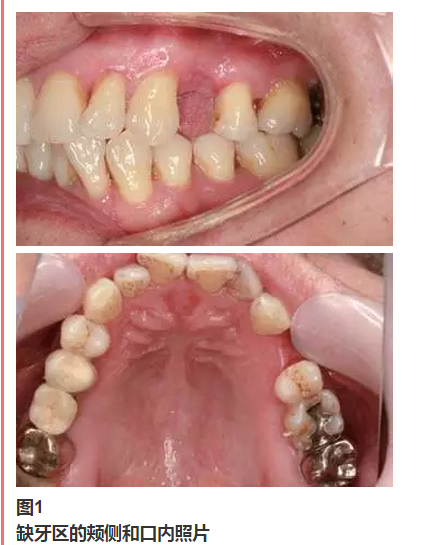

患者牙位24因根折拔除,3個(gè)月后要進(jìn)行牙種植手術(shù),患者不希望做二期手術(shù)。

從圖1可以看出患者缺牙區(qū)的間隙充足,牙齦健康,頰側(cè)軟組織略有凹陷。